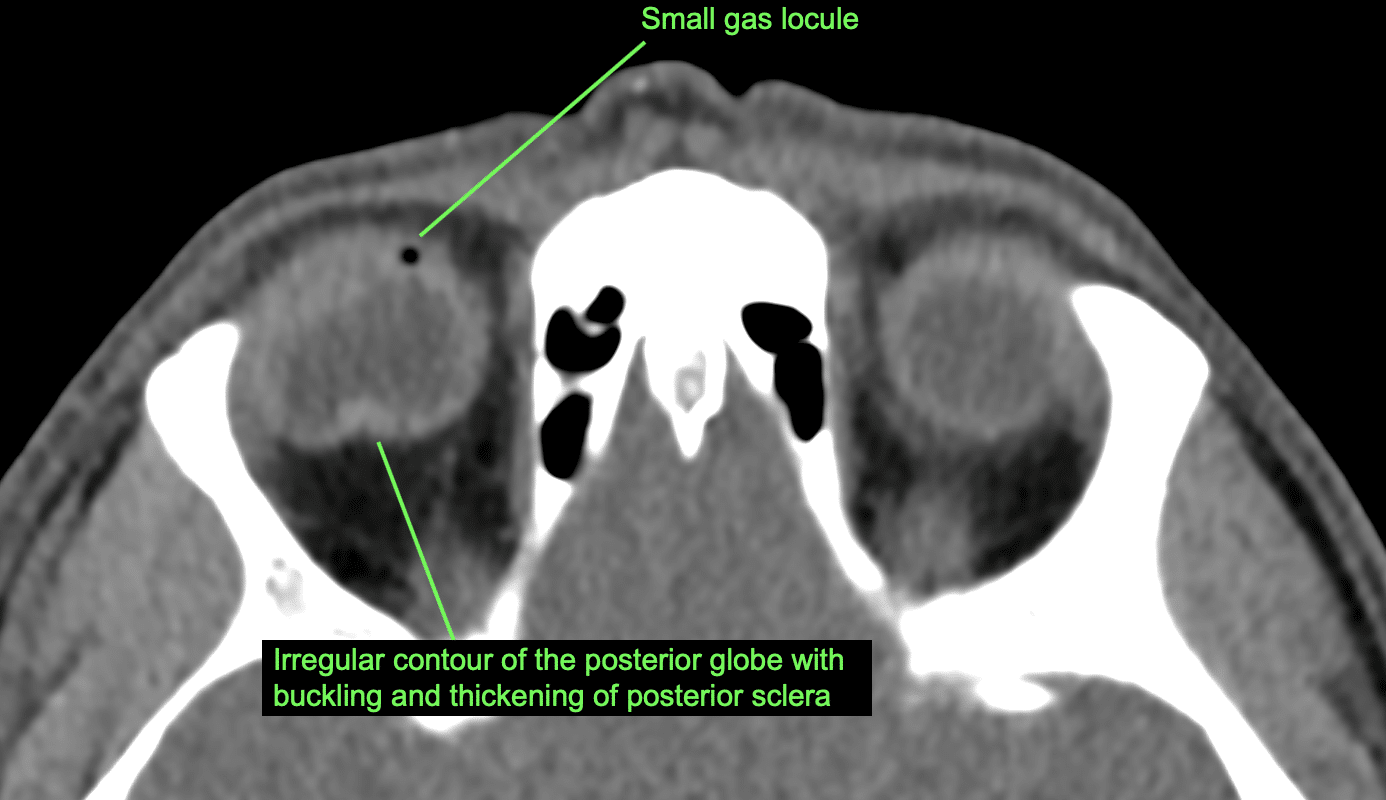

CT Case 020 • LITFL • CT scan interpretation